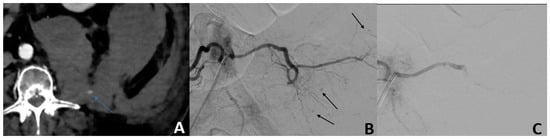

Angiographic active bleeding was detected in 50/56 (89.3%) patients, resulting in 6/56 (10.7%) patients being treated by empiric TAE. Procedures were performed using a gelatine sponge for 32/56 (57.2%) patients, microparticles for 11/56 (19.6%) patients; N-Butyl Cyanoacrylate (NBCA) for 4/56 (7.1%), with a combination of sponge and microparticles for 2/56 (3.6%) patients; a combination of gelatine sponge and NBCA in 1/56 (1.8%) patients; and a combination of coils, gelatine sponge, and particles for 1/56 (1.8%) patients (Figure 1).

The main arteries embolized were: the lumbar artery in 30/56 (53.6%) patients, the inferior epigastric artery in 15/56 (26.8%) patients, and the ilio-lumbar artery in 14/56 (25.0%) patients. Multiple arteries were embolized in 8/56 (14.3%) patients. Two hematomas at the puncture site were reported (Grade A). Pre-procedure data are detailed in Table 3.

Figure 1. Isolated blood loss in a 74-year-old patient 2 days after cardiac surgery. (A) The MDCT scan showed active bleeding (blue arrow) from a large left retroperitoneal hematoma. (B) Angiography confirmed active multifocal bleeding from the left L5 lumbar artery (black arrows). (C) After embolization with NBCA, the control showed no opacification of the distal branches of the left L5 lumbar artery.